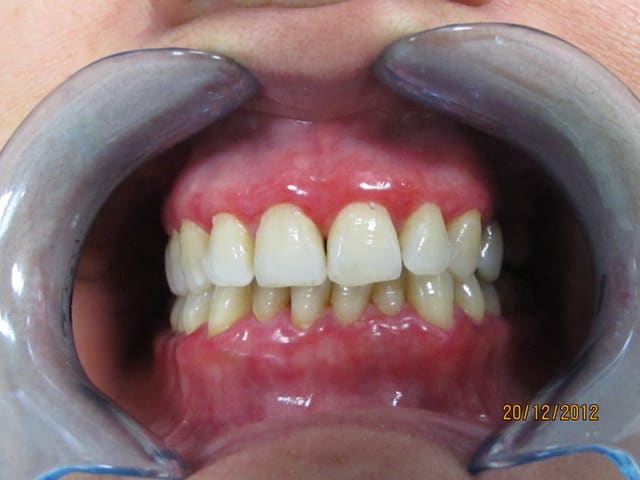

Je viens de voir cette patiente, qui consulte pour le problème esthétique lié à la couleur très gênante de sa gencive.

Cette patiente, originaire d’Afrique du nord a la trentaine, pas de pathologie générale connue, pas d'allergie.

elle a été traitée il y a 2 mois par surfaçage et motivation aux soins locaux qu'elle applique plutôt sérieusement.

Au sondage pas de poche, quasiment pas de saignement.

La couleur rouge s'estompe à la pression, on sent la gencive très fine et lisse.

Aucune douleurs.

Ca me rappel le cas d'une patiente qui avait une penphigoîde, qu'en pensez vous ? On voit sur les photos des trace qui pourrait laisser penser à des desquamations de bulles.